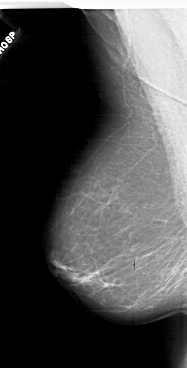

A_1718_1.RIGHT_CC

RIGHT_CC LINES 6481 PIXELS_PER_LINE 3346 BITS_PER_PIXEL 12 RESOLUTION 43.5 OVERLAY

FILE: A_1718_1.RIGHT_CC.OVERLAY

TOTAL_ABNORMALITIES 1

ABNORMALITY 1

LESION_TYPE MASS SHAPE FOCAL_ASYMMETRIC_DENSITY MARGINS ILL_DEFINED

ASSESSMENT 4

SUBTLETY 4

PATHOLOGY BENIGN

TOTAL_OUTLINES 1

BOUNDARY